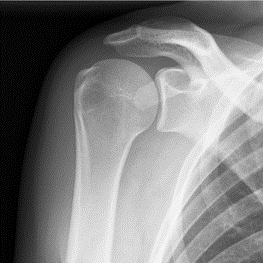

De reversed prothese of omgekeerde schouderprothese is een oplossing voor hen die een versleten schouder hebben waarbij de rotator cuff heel zwaar en onomkeerbaar beschadigd is. Daardoor beweegt de schouder abnormaal in zijn gewricht en krijgt men secundair kraakbeen beschadiging.

Voor de patiënt heeft dit tot gevolg dat de schouder pijn geeft bij beweging en tijdens de nacht.

Een belangrijker gegeven is het krachtsverlies die er optreedt bij heffen en gebruik, tot zelfs een onmogelijkheid om de arm in de hoogte te steken. Een pseudo verlamming.